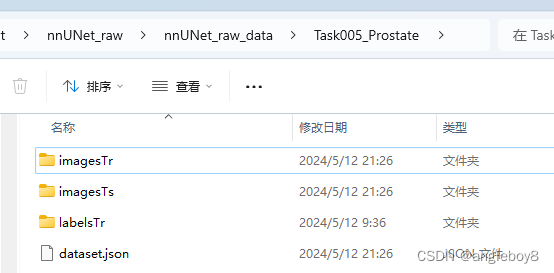

nnUNet_convert_decathlon_task -i 自己存放数据集的路径\Task05_Prostate运行结果目录如下:

以imagesTs为例: